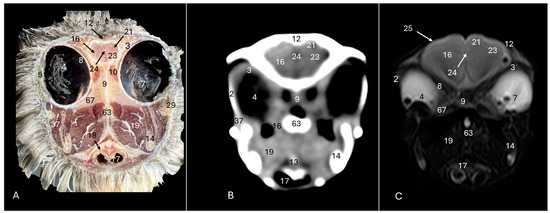

3. Result

3.1. Anatomical Sections

3.2. Computed Tomography (CT)

3.3. Magnetic Resonance Imaging (MRI)